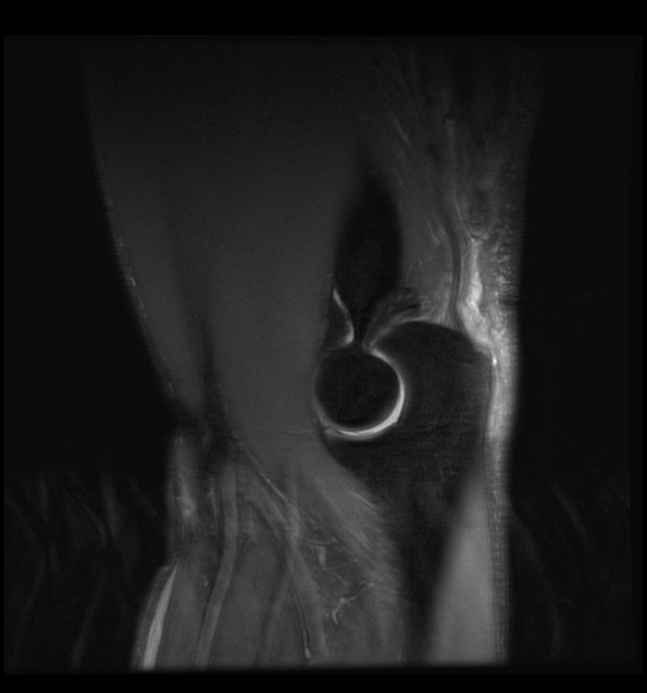

• Imaging Of The Elbow

• Evaluation And Management Of Triceps Ruptures

• Distal Biceps And Triceps Injuries

• Triceps Tendon Tear U2013 Pro Sports Injuries